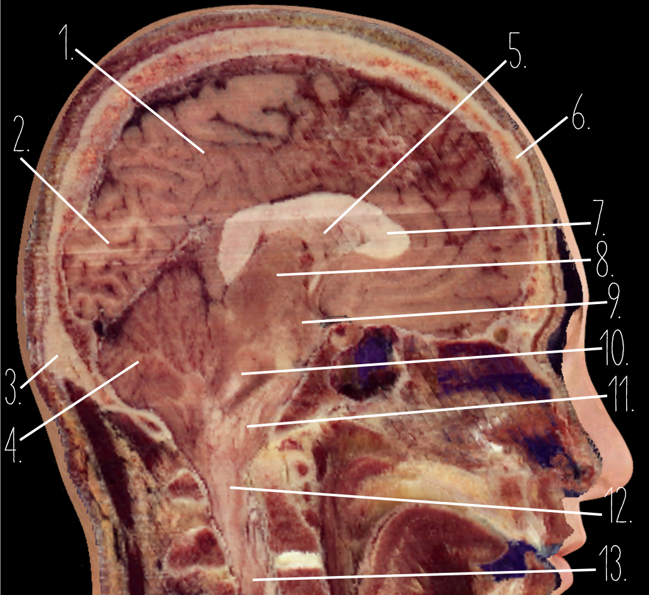

Brain Cross Sectional

1

Frontal Bone

2

Frontal Lobe

3?

Falx Cerebri

4?

Gray Matter

5?

White Matter

6?

Sulcus

7?

Gyrus

8?

Fissure

1?

Parietal Lobe

2?

Cerebellum

3?

Occipital Bone

4?

Cerebellum

5?

Lateral Ventricle

6?

Frontal Bone

7?

Corpus Callosum

8?

Thalamus

9?

Hypothalamus

10?

Midbrain

11?

Pons

12?

Medulla Oblongata

13?

Spinal Cord